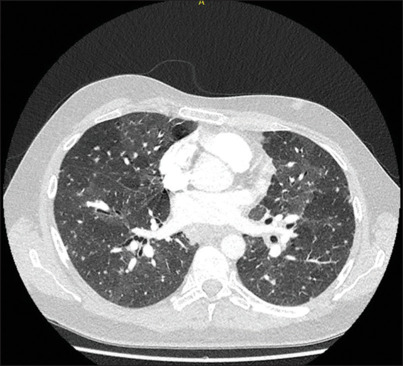

Sarcoidosis is a disease of unknown etiology, characterized by noncaseating granulomas. Generally, the condition primarily manifests in the lungs. Extrapulmonary involvement is common, but localization in the gastrointestinal system is rare. Here, we present the case of a 37-year-old male who became increasingly hemodynamically unstable during the diagnostic workup for sarcoidosis due to acute variceal bleeding. The underlying mechanism was later attributed to portal hypertension caused by hepatic involvement of the disease. This case demonstrates the importance of considering variceal hemorrhage as a rare but life-threatening complication of gastrointestinal localization of sarcoidosis.